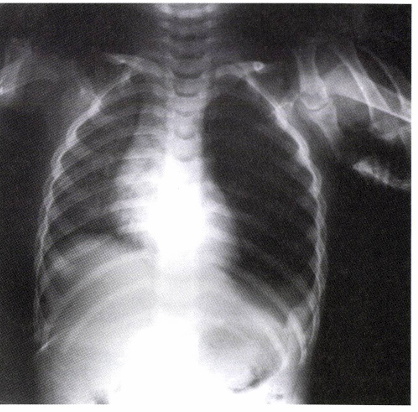

• 방사선 검사: 들숨 및 날숨 시의 흉부 X선(Chest X-ray)

• 이물이 공기를 가두는 '체크 밸브(check valve)' 효과를 일으킬 경우, 호기 시(expiration) 이물이 있는 쪽 폐의 과팽창(hyperinflation) 및 종격동 변위(mediastinal shift)가 관찰될 수 있음.